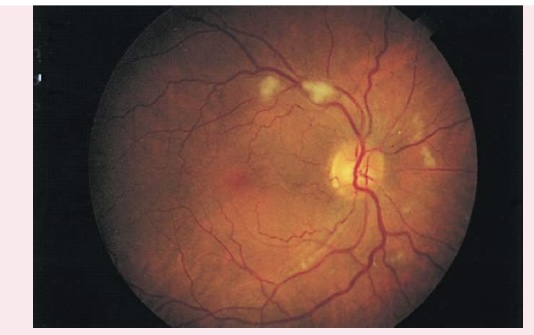

PAPILLEDEMA

Swollen optic disc

Blurred margins

Hyperemic appearance from accumulation of excess blood

Visible and numerous disc vessels

Lack of visible physiologic cup

GLAUCOMA

• Enlarged physiologic cup occupying more than half of the disc's diameter

• Pale base of enlarged physiologic cup

• Obscured and/or displaced retina vessels

COTTON WOOL PATCHES

Also known as soft exudates, cotton wool patches have a fluffy cotton ball appearance, with irregular edges.

Appear as white or gray moderately-sized spots on retinal background

Caused by arteriole microinfarction

Associated with diabetes mellitus and hypertension